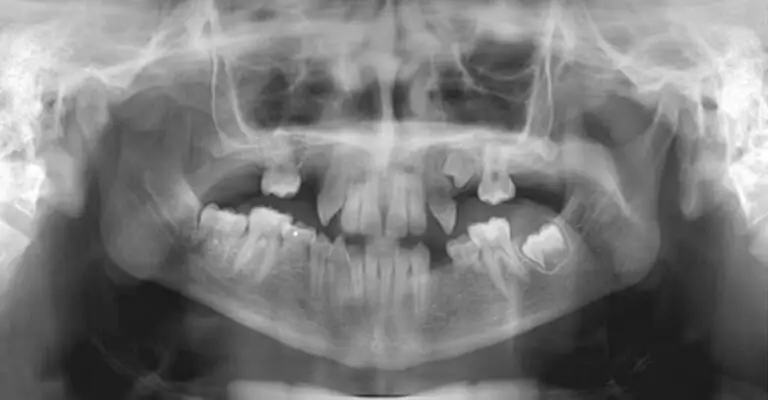

Investigadores japoneses han desarrollado un medicamento experimental que podría permitir el crecimiento de nuevos dientes en humanos, anunciando el inicio de pruebas en septiembre. El Hospital Kitano de Osaka dirigirá el ensayo clínico con 30 hombres de 30 a 64 años que carecen de al menos un diente. El tratamiento, administrado intravenosamente durante once meses, busca evaluar su seguridad y eficacia, tras demostrar resultados libres de efectos secundarios en estudios con animales.

El proyecto se basa en el anticuerpo USAG-1, identificado por su papel en la inhibición del crecimiento dental en animales. Descubrimientos recientes de la Universidad de Kioto revelaron un anticuerpo monoclonal que podría revertir este efecto, inspirando la investigación actual. Si los resultados son positivos, el siguiente paso es adaptar el tratamiento para niños con deficiencias dentales congénitas, con la meta de un medicamento disponible para el año 2030.